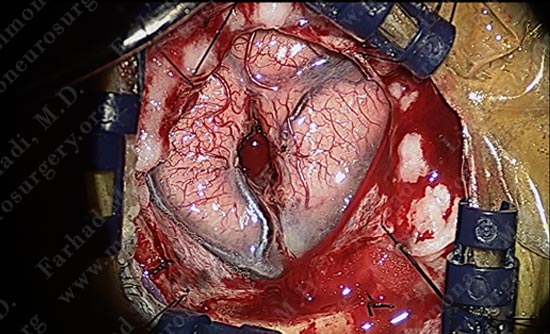

While patient is awake and conversing with Dr. Limonadi, motor cortex stimulation was utilized to locate the motor cortex.

Motor cortex was identified and is colored green. The tumor is deep and within the parenchyma of this gyrus.

Using a scalpel, the arachnoid between the motor strip and adjacent gyrus is carefully opened without damaging the adjacent vessel.

Micro-instruments are utilized in opening the interval between the two gyri underneath which the tumor is hidden. Patient is being examined in short intervals.

The superficial pole of the tumor is outlined in green.

The tumor is nicely dissected out as patient is talking to the surgeon and being examined by the surgical team.

Tumor is removed without any injury to the motor cortex or adjacent neuro-vascular structures. Patient is awake and doing well with no neurological deficit.